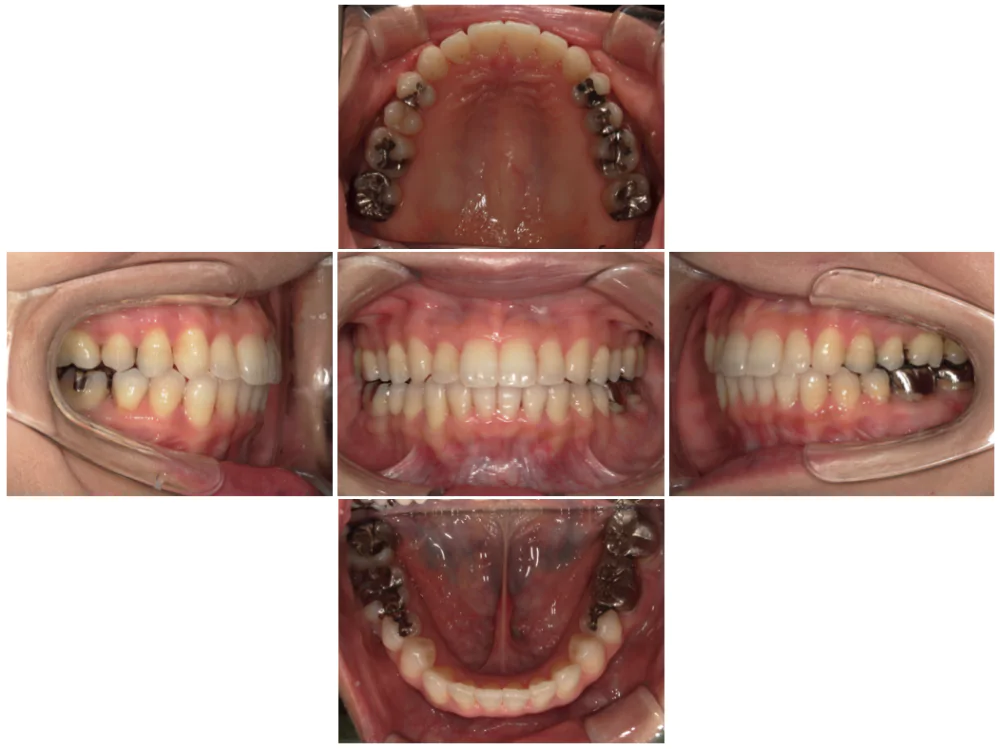

症例3

| 来院時の主訴 | 歯の間の隙間を閉じたい |

| 医院での対応や適用装置 | マウスピース矯正装置を使用して主訴である歯の間の隙間を閉じて改善を行いました。 歯の隙間の原因は飲み込み時に舌を前に出してしまう癖だと考えられましたので、 トレーニングを行い癖も無くなりました。 |

| 通院期間 | 6ヶ月 |

| 通院回数 | 5回 |

| 治療費用総額 | 577,500円(税込) |

| リスクと副作用 | 矯正治療による歯の移動に伴う痛み、歯根吸収、虫歯 |